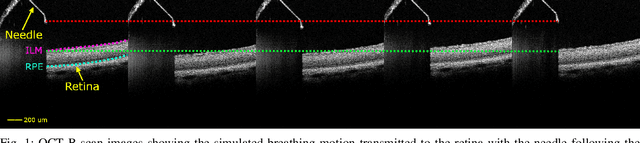

Exudative (wet) age-related macular degeneration (AMD) is a leading cause of vision loss in older adults, typically treated with intravitreal injections. Emerging therapies, such as subretinal injections of stem cells, gene therapy, small molecules or RPE cells require precise delivery to avoid damaging delicate retinal structures. Autonomous robotic systems can potentially offer the necessary precision for these procedures. This paper presents a novel approach for motion compensation in robotic subretinal injections, utilizing real-time Optical Coherence Tomography (OCT). The proposed method leverages B$^{5}$-scans, a rapid acquisition of small-volume OCT data, for dynamic tracking of retinal motion along the Z-axis, compensating for physiological movements such as breathing and heartbeat. Validation experiments on \textit{ex vivo} porcine eyes revealed challenges in maintaining a consistent tool-to-retina distance, with deviations of up to 200 $\mu m$ for 100 $\mu m$ amplitude motions and over 80 $\mu m$ for 25 $\mu m$ amplitude motions over one minute. Subretinal injections faced additional difficulties, with horizontal shifts causing the needle to move off-target and inject into the vitreous. These results highlight the need for improved motion prediction and horizontal stability to enhance the accuracy and safety of robotic subretinal procedures.